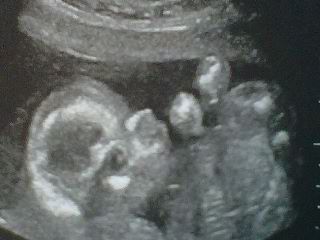

We are now expecting our baby girl in June!